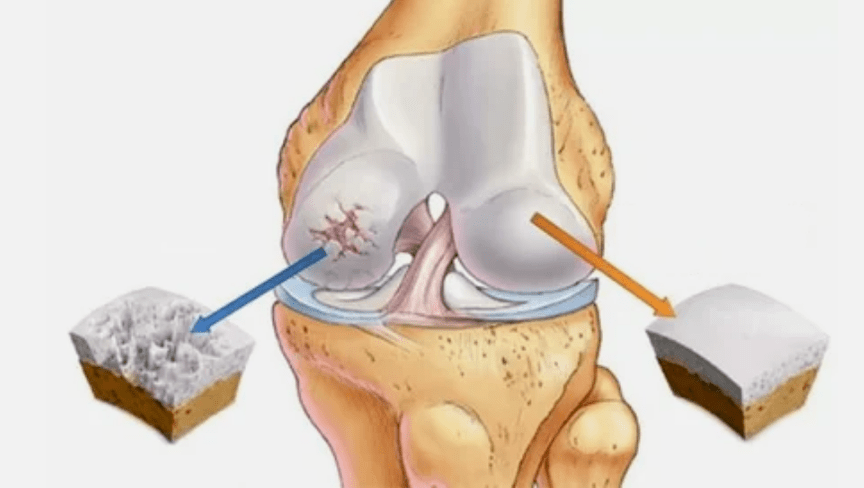

- Primārais bojājums ietekmē hialīna skrimšļus. Asinsrites traucējumu gadījumā notiek patoloģiskās jaudas pasliktināšanās. Tas ir pirmais solis vai iemesls, kas var rasties artroze.

- Hialīna pārklājuma patoloģijas. Skrimšļa retināšana noved pie tā patoloģisko audu - kaulu struktūru aizstāšanas.

- Anomāli izaugumi parādās skrimšļos - osteofītos.

- Skrimšļa un kaulu dabiskās anatomijas pārkāpums izraisa veselīgu skrimšļa zonu pārslodzi. Locītavu audu iznīcināšana bez ārstēšanas pastāvīgi progresē un izraisa invaliditāti.

Kad palielinās slimības pakāpe, patoloģiskie procesi joprojām tiek saasināti. Galu galā visi hialīnu skrimšļi tiek iznīcināti.